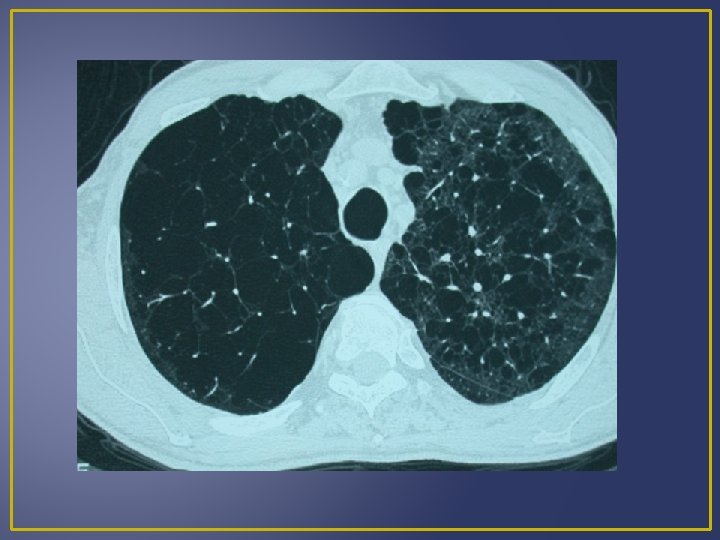

On distingue 4 types d’emphysèmes selon la localisation des lésions dans l’acinus : 1 - Emphysème panlobulaire: (Pan-acinaire) : EPL C’est l’ensemble de l’acinus qui est touché associé à des lésions vasculaires avec fenestration puis destruction de leurs parois et confluence des espaces aériens distaux. Il s'agit d'un emphysème diffus prédominant aux lobes inférieurs. Ce type d’emphysème est retrouvé chez les patients porteurs d’un déficit en α 1 antitrypsine, les sujets âgés non-fumeurs et les fumeurs sans déficit en α 1 antitrypsine. 2 - Emphysème centrolobulaire(centro-acinaire) ECL Les lésions sont retrouvées en position centrale de l’acinus alors que les alvéoles sont préservées. L’atteinte prédomine souvent dans la partie supérieure des lobes inférieurs et au niveau des lobes supérieurs, ce type d’emphysème est rencontré quasi exclusivement chez les fumeurs.